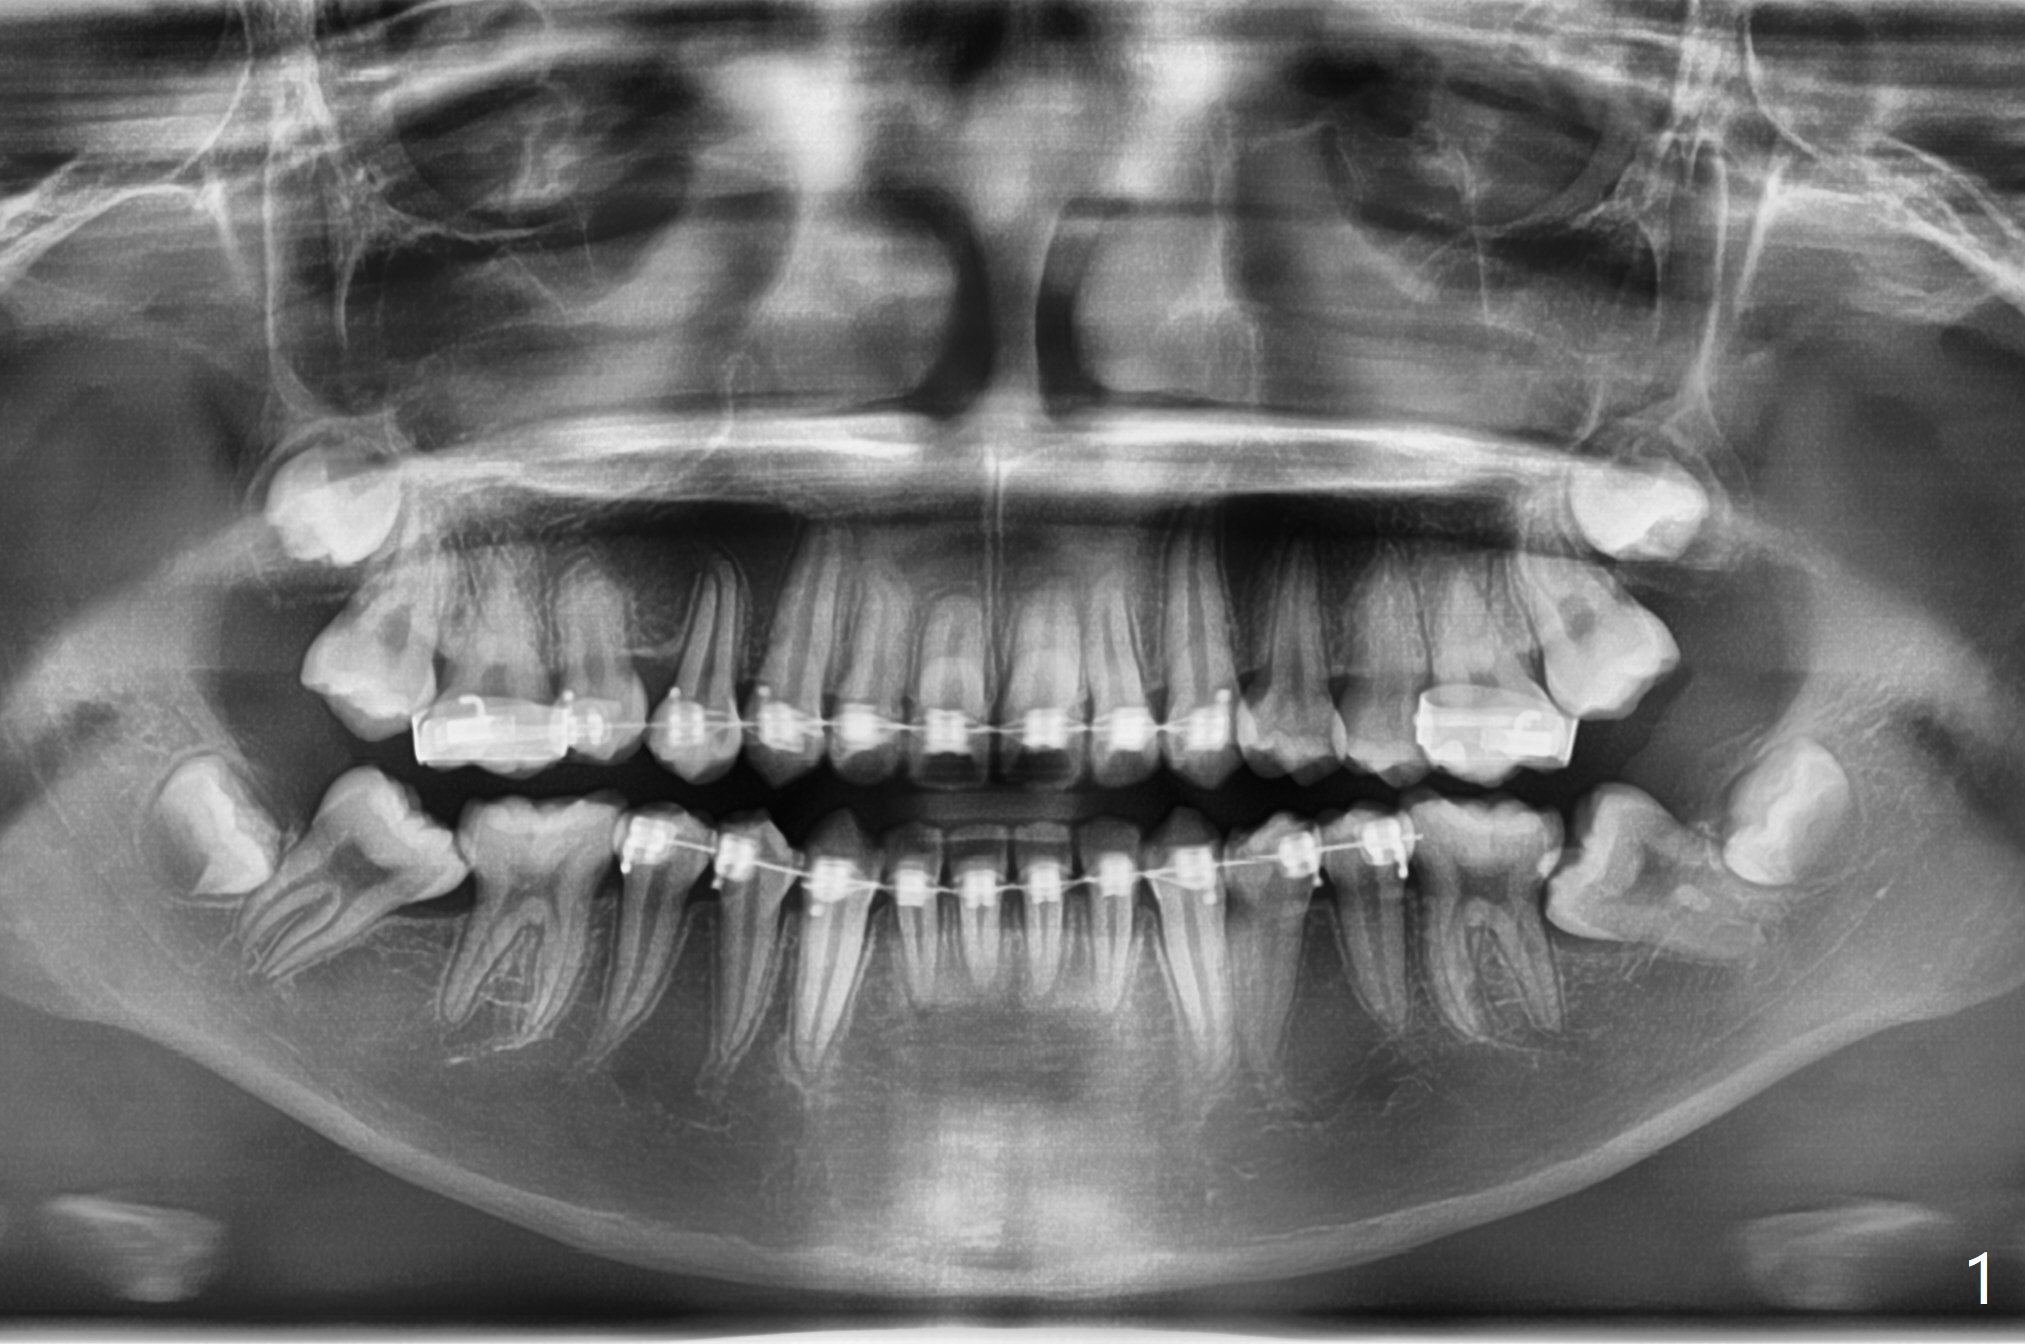

13岁男在矫正医生诊所矫正三年(上中切牙牙根短,图一),转来拔除下颌智齿以助于第二磨牙upright。左侧先拔除,切除三个小块颊侧骨板,保留其中一个与异体骨一起植入牙槽窝近中部分。右侧拔除时,索性切除一个大块颊侧骨板(图二),智齿拔除后,近中牙槽窝放置异体骨(皮质,图三,五:*),远中胶原塞(C),放回颊侧骨板(图四)。Return to Plug Xin Wei, DDS, PhD, MS 1st edition 11/03/2020, last revision 11/03/2020